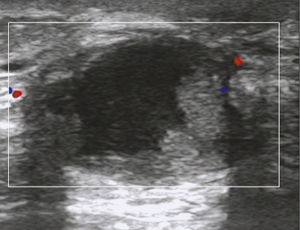

All of 178 patients had breast mass with unclear boundaries, ranging from 2~14 cm in diameter. Of them, 134 patients (75.3%) complained of skin ulcerations and swelling (Figure 1), 127 (71.3%) with abscesses (Figure 2), 18 (10.1%) with peau d’orange sign, which was easily confused with breast cancer (Figure 3), 6 (3.4%) with skin erythema on legs.

USG showed ill-defined, hypoechoic, heterogeneous lesions in most of the patients with GLM. Sometimes the breast lesion had specific signs including ‘Funnel sign’, ‘tunnel sign’ or ‘quicksand sign’, while it complicated with abscesses (Figures 4-6). According to the previous experience (5,11), 26 patients underwent mammography in our early study, which did not show characteristic signs of the lesion. In late study, patients did not had mammography as a routine examination because of its limitations such as the aggravation of the pain after mammography.